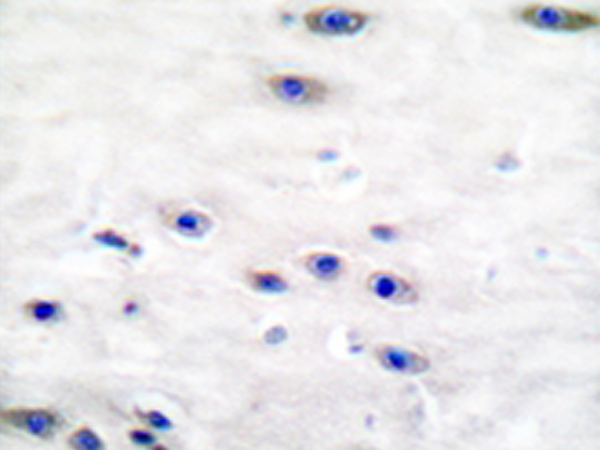

IHC positive control: |

Human brain tissue |